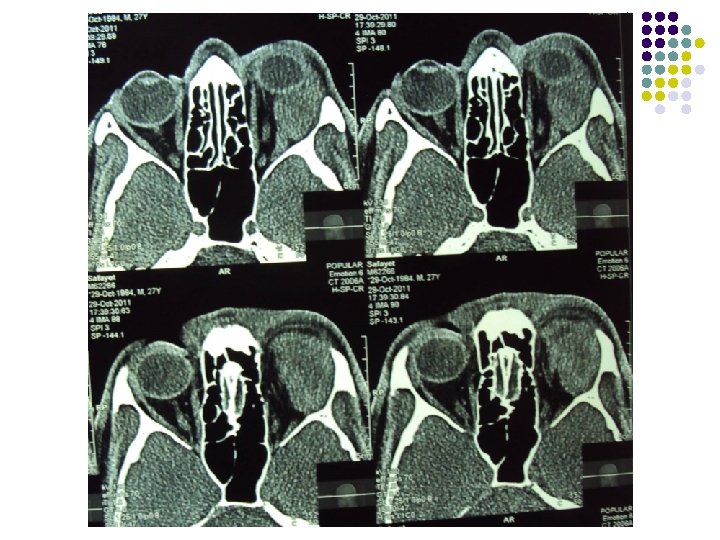

CT Scan of Brain

Clinical Diagnosis Retrobulbar solid tumour on left orbit